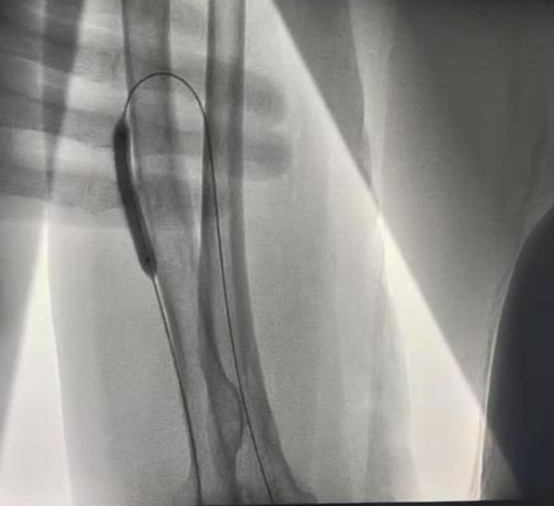

近日,在介入科大力协作和上级医院专家指导下,我院肾内科成功开展首例DSA引导下动静脉内瘘球囊扩张术(PTA under DSA guidance),顺利为透析患者打通“生命线”。

现年72岁的陆奶奶是外院一位靠血液透析维持生命的尿毒症患者,日前因左前臂人工内瘘功能不良再次前来我院就诊。入院后经查发现患者内瘘吻合口明显狭窄,进而导致内瘘功能不良,不能透析使用。患者高龄,为了保护和充分利用患者宝贵的血管资源,科室透析通路团队经过充分评估,决定对陆奶奶进行DSA引导下动静脉内瘘球囊扩张术。

经过充分沟通同意和术前积极准备,近日,在介入科协作和上级医院专家指导下,顺利经皮下穿刺患者动静脉内瘘,然后在DSA引导下将球囊送入血管的狭窄部分进行扩张。手术过程顺利,患者伤口小,痛苦轻,出血少。术后患者内瘘处听诊血管杂音清晰,可触及明显震颤,远心端血管充盈显著,超声评估内瘘吻合口血流量达标,手术十分成功。经过悉心指导进行内瘘功能锻炼和保护后,患者已于日前满意出院,回当地继续透析,同时科室密切随访。